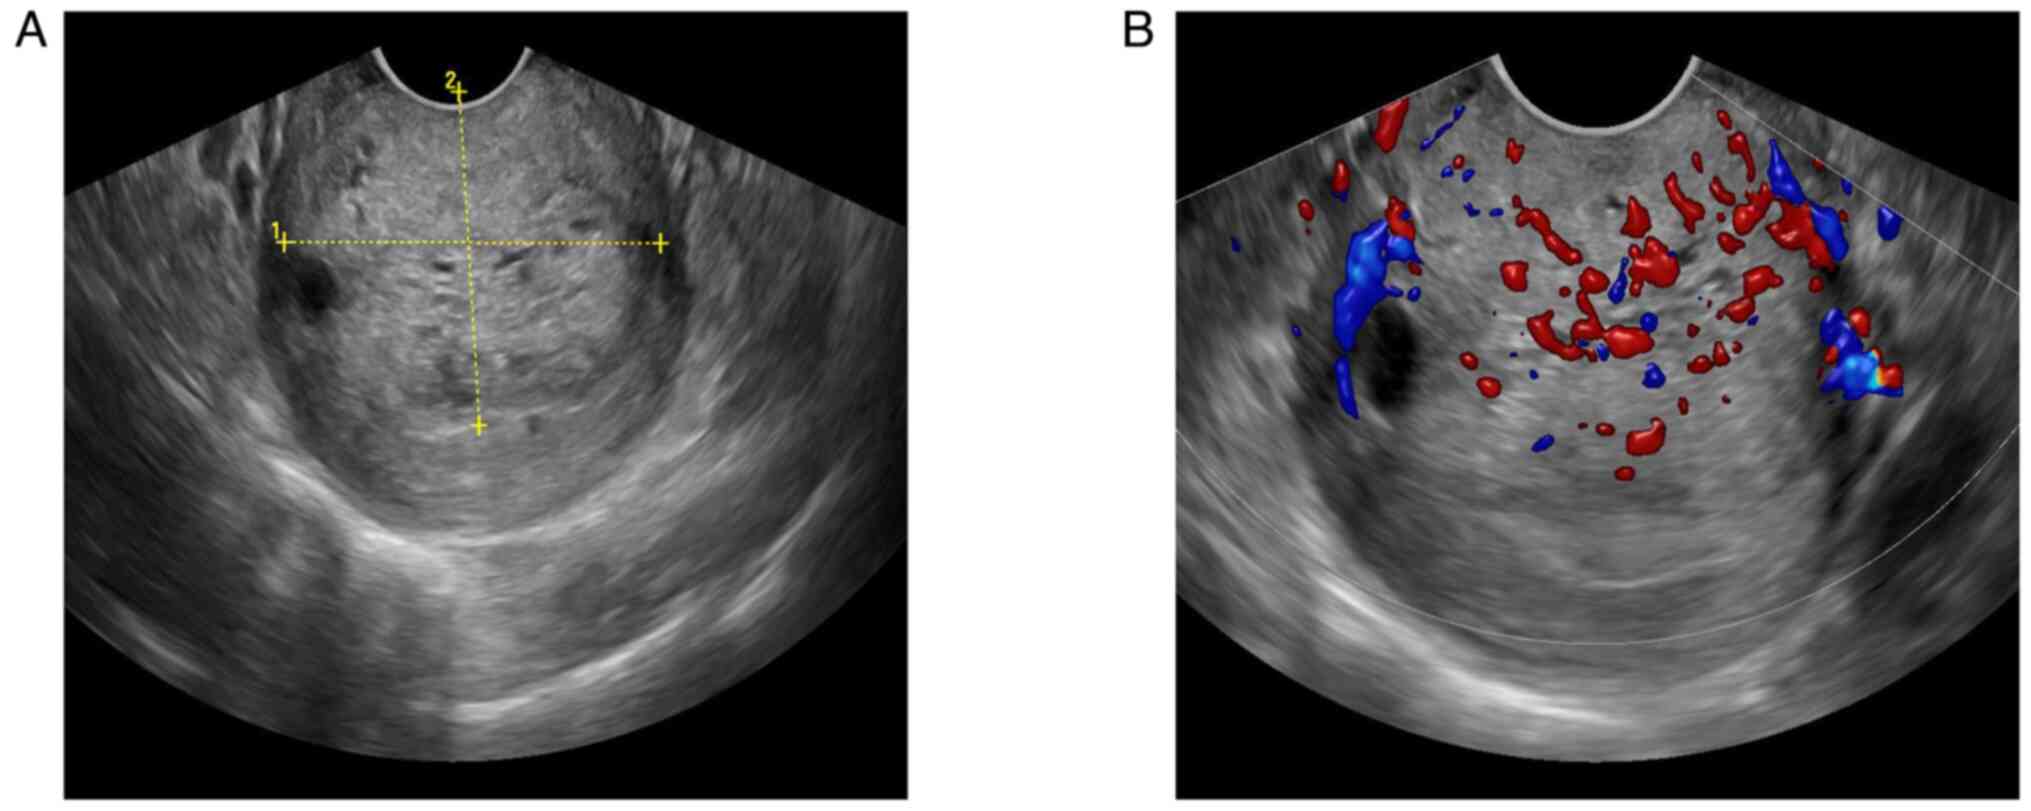

Patient B, a 39-year-old woman, presented to The Women's Hospital, School of Medicine, Zhejiang University (Hangzhou, China) in August 2022 with increased vaginal discharge for 6 months, which was mucoid and clear in color, accompanied by frequent urination and no abnormal uterine bleeding. The patient had no family history of genetic, neurological, psychiatric, infectious or similar diseases. The results of the TCT showed that the patient was NILM and HPV-negative. The TVUS (Fig. 6A and B) showed heterogeneous echo areas in the anterior lip of the neck with clear boundaries, regular shapes, multiple cystic areas and color Doppler demonstrated a rich blood supply. The shear wave elasticity (Fig. 7) showed moderately hard texture, indicating a diagnosis of GEA. For further diagnosis, CEUS was performed and the results (Fig. 8A and B) suggested that the hypoechoic area of the anterior cervical lip began filling at 14 sec and reached the peak at 19 sec. The tumor tissue showed rapid hyperenhancement and then slowly decreased. Pelvic contrast-enhanced MR (Fig. 9A and B) suggested the presence of a leiomyoma lesion on the anterior lip of the cervix, with clear boundaries and patchy long T2 signals, which showed heterogeneous enhancement after enhanced scanning, and so cervical leiomyoma with degeneration was considered. The cervical biopsy pathology (Fig. 10A and B) was indicative of GEA. After obtaining informed consent, the patient underwent an abdominal radical hysterectomy, pelvic lymph node dissection, bilateral salpingo-oophorectomy and intestinal adhesion lysis at the Women's Hospital, School of Medicine, Zhejiang University. The postoperative pathological (Fig. 11A and B) diagnosis was GEA, which infiltrated the entire interstitial layer and involved the fornix. The tumor did not invade the periuterine, bilateral ovarian vessels and greater omental tissue. A total of 33 lymph nodes were not invaded by the tumor. The immunohistochemical staining results were: Insulin-like growth factor II m-RNA-binding protein 3 (+), D2-40 (vascular +), estrogen receptor (−), progesterone receptor (−), carcinoembryonic antigen (local +), P53 (wild-type), low molecular weight cytokeratin (+), P16 (+), Ki-67 (+ 60%), MUC-6 (+), programmed cell death protein 1 (tumor proportion score:-; combined positive score:<1) and programmed death ligand 1 (tumor proportion score:-; combined positive score:<1). The results were in accordance with FIGO stage IIA2. Preoperative examination showed that the CA199 tumor marker level of the patient was 401.9 U/ml (normal reference value, ≤37.0 U/ml) (18). At 2 months post-surgery, the CA199 tumor marker level decreased to 86.0 U/ml (normal reference value, ≤37.0 U/ml). At 8 months post-surgery, the CA199 tumor marker level had recovered to 25.4 U/ml (normal reference value, ≤37.0 U/ml). The patients were followed up every 3 months for 1–2 years post-operation, and every 6 months for 3–5 years thereafter. Currently, patient B has been followed up for nearly 2 years with no evident recurrence. The key messages in this case are the need to accurately understand the typical imaging findings of GEA and the fact that the use of a deep biopsy or conical incision for suspicious lesions is necessary.

Figure 6.

Transvaginal ultrasound images in case two. (A) A solid mass in the cervix with multiple small dark areas. (B) Color Doppler image of the same mass demonstrating internal vascularity.

The most common TVUS finding of GEA is cervical hypertrophy with multiple cystic lesions (5). Park et al (8) proposed that 60% of GEA lesions were multilocular cystic, 40% were solid and 50% of cystic lesions were accompanied by solid components. The study also indicated that color Doppler showed a rich blood supply in GEA lesions, which is helpful for the diagnosis of GEA. In the present study, the two cases were similar to those observed in the literature, whereby multiple cystic dark areas were seen in the cervix, and color Doppler showed an abundant blood supply. By contrast, patient A showed irregular thickening of the cyst wall, viscous fluid in the interior and small honeycomb-like changes in the solid part of the lesion. The cystic dark area of the cervix in patient B communicated with the cervical surface to form a tunnel-like change, which was helpful for the diagnosis of GEA.